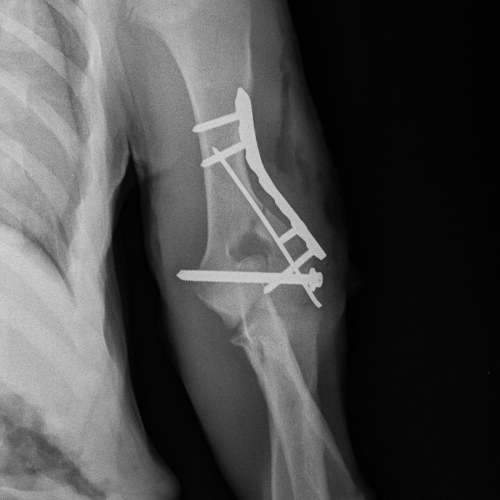

El servicio de traumatología está dirigido por Enrique Senís, especialista en traumatología y ortopedia por la Universidad Complutense de Madrid . Estamos orientados al diagnóstico y tratamiento de patologías del sistema musculoesquelético, incluyendo fracturas, luxaciones, rotura de ligamento cruzado y demás alteraciones articulares y deformidades óseas.

Disponemos de medios diagnósticos avanzados y aplicamos técnicas quirúrgicas de última generación en osteosíntesis, estabilización articular y corrección de deformidades, con el objetivo de restaurar la funcionalidad y minimizar el dolor en nuestros pacientes.